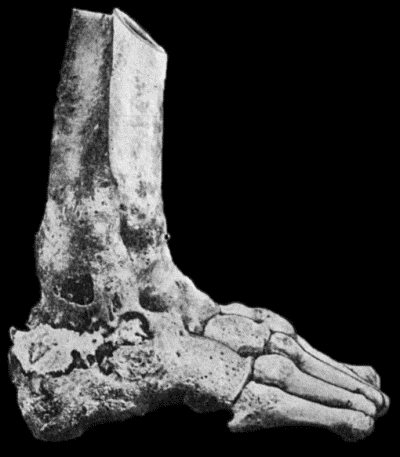

Another modification is to raise the flap but leave it connected at both ends like the piers of a bridge; this method is well suited to defects of skin on the dorsum of the fingers, hand and forearm, the bridge of skin is raised from the abdominal wall and the hand is passed beneath it and securely fixed in position; after an interval of 14 to 21 days, when the flap is assured of its blood supply, the piers of the bridge are divided (Fig. 1). With undermining it is usually easy to bring the edges of the gap in the abdominal wall together, even in children; the skin flap on the dorsum of the hand appears rather thick and prominent—almost like the pad of a boxing-glove—for some time, but the restoration of function in the capacity to flex the fingers is gratifying in the extreme.

Fig. 1.—Ulcer of back of Hand covered by flap of skin raised from anterior abdominal wall. The lateral edges of the flap are divided after the graft has adhered.